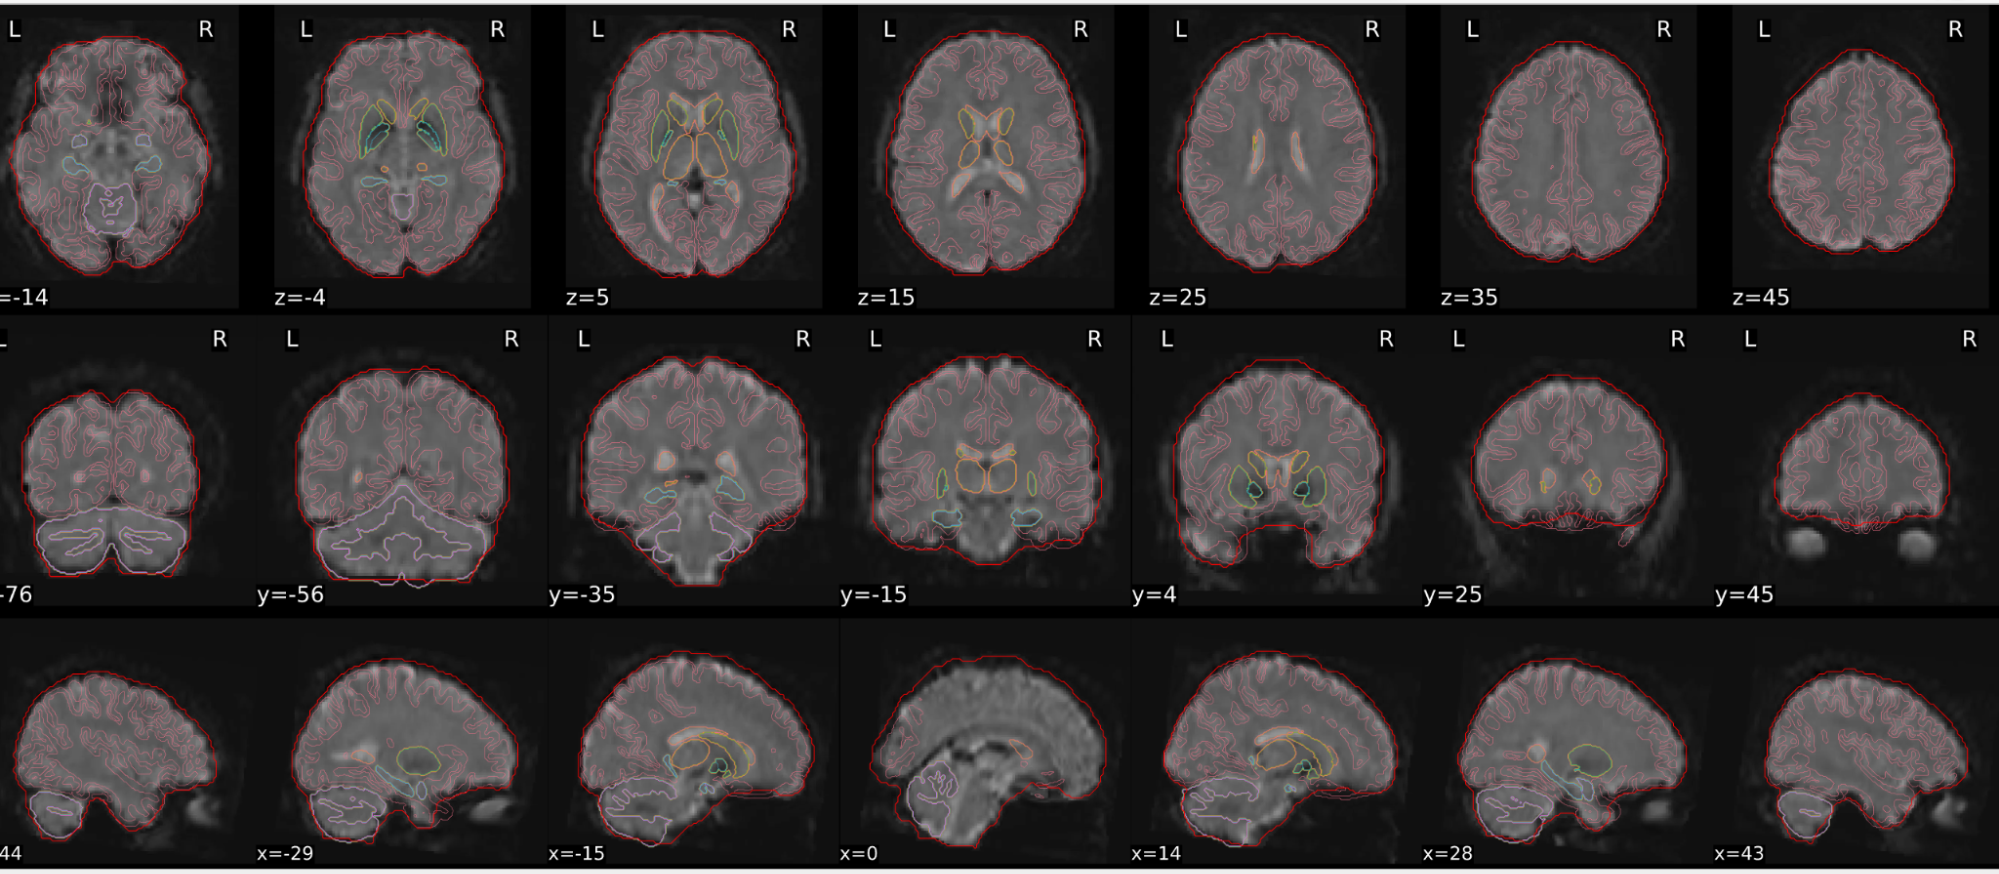

EPI spatial normalisation

This QC step shows the registration of the EPI image to MNI space.

Example of a good subject

- If the registration performed well, you should see an overlap (i.e., correspondence of structures) between the MNI template and the EPI registered to the MNI space.

- If parts of the brain are missing due to the scanner field of view, this is fine. For example, the cerebellum may be cut off for a participant with a large head.

Example of a bad subject

- In case of poor registration, you should see a misalignment of the EPI and the MNI template

Summary

| good | bad |

|---|---|

| Overlap (i.e. match of structures) between the MNI template and the EPI registered in the MNI space | Misalignment of the EPI and the MNI template |

| If parts of the brain are missing because the field of view of the scanner is limited, the EPI spatial normalisation does not have to be excluded e.g. cerebellum cut off in person with large head |

If parts of the brain are missing because the field of view of the scanner is limited, the EPI spatial normalisation does not have to be excluded (e.g. cerebellum cut off in person with large head)